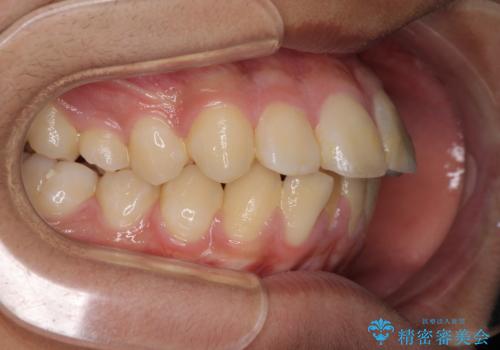

膨らんだ口元 ワイヤー装置での抜歯矯正

- 口元の突出感を気にして来院された患者様です。

上下前歯が著しく前突している状態であったので、上下左右の第1小臼歯4本を抜歯し、ワイヤー装置にて矯正治療を行うこととしました。

小学生の頃に上顎前歯をぶつけ、歯の一部が破損している状態であったので、歯根が歯槽骨と癒着して移動しない可能性がありましたが、無事に治療を終えることができました。